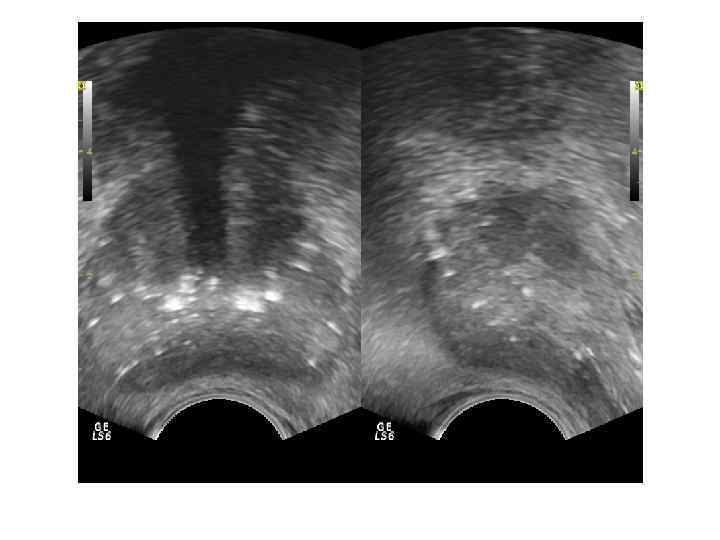

Брахитерапия– введение миниатюрных специально изготовленных источников радиоактивного излучения на основе Йода-125 непосредственно в опухоль без поражения прилегающих органов и тканей. После брахитерапии сонографически в ткани простаты выявляются множественные гиперэхогенные включения с эффектом «хвоста кометы» , на этом фоне опухолевые узлы визуализировать сложно, оценка эффективности проводится путем исследования уровня PSA.